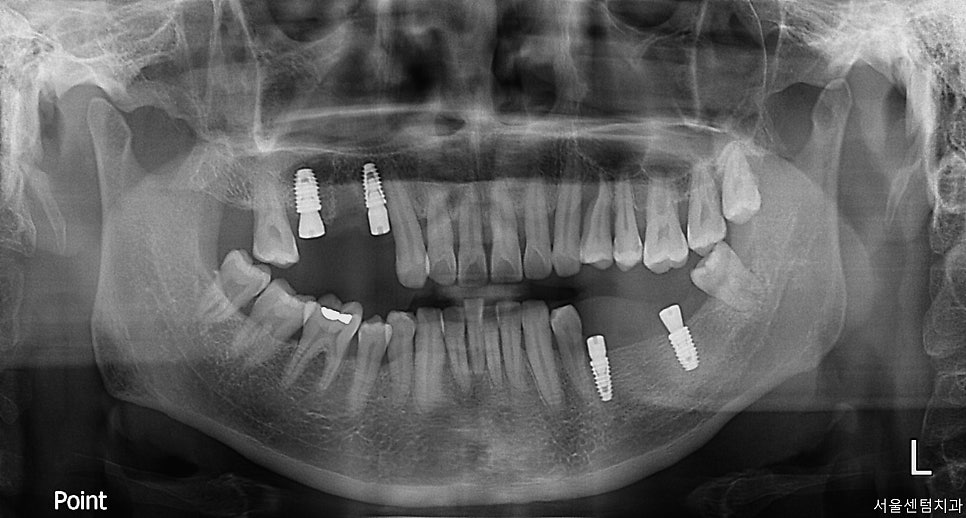

임플란트 치료 어금니 앞니 전치부 보철치료 진행 결과

치료 기간이 좀 긴 장기적인 치료였는데요.

꽤 오래 걸렸지만 환자분이 만족할 만한

결과로 치료가 성공적으로 종료되었습니다.

어금니와 앞니 두 군데가 문제가 있을 경우에

무작정 다 치료를 하는 게 아닌

어떻게 치료를 할 것인지도 중요한 부분입니다.

꼭 교합을 살피고 치료를 해야 하며

치아 자체에는 문제가 더 없는지도

꼼꼼히 살펴야 하는 케이스였습니다.